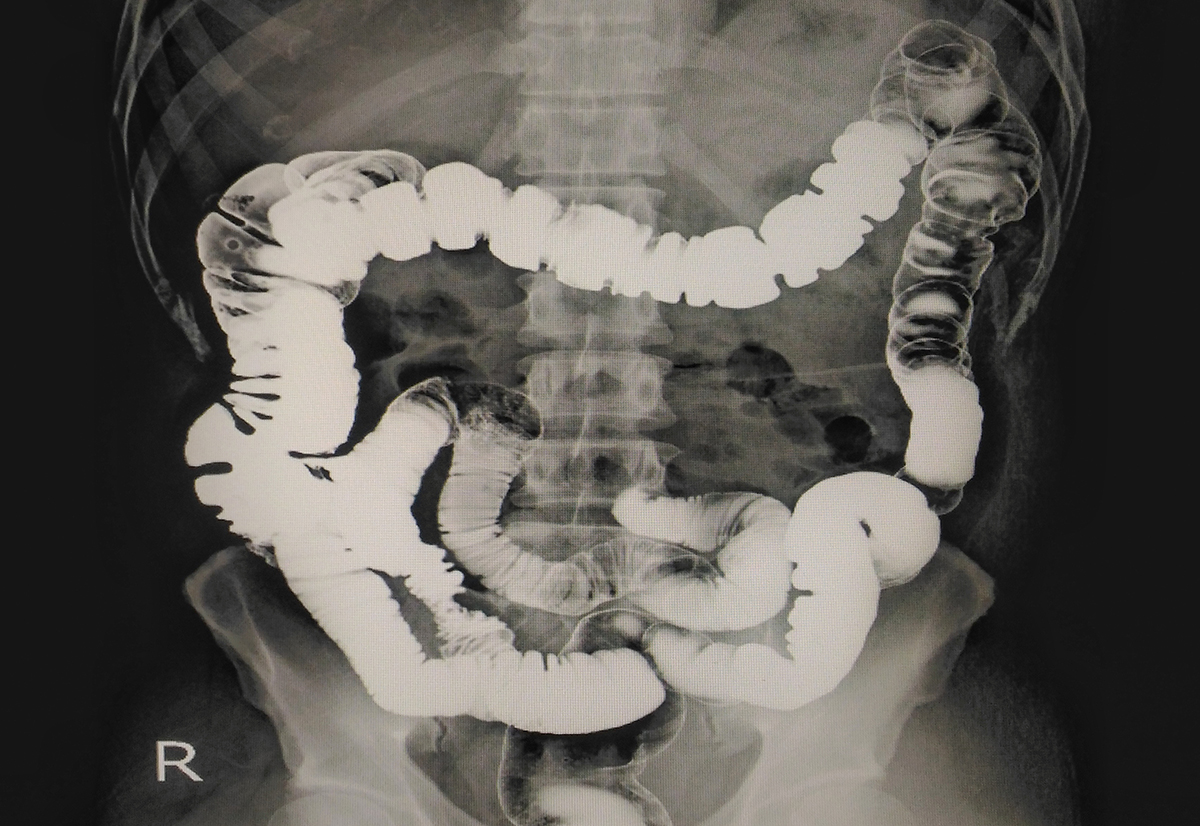

ナイアシンが欠乏すると、「4D症状」として知られる皮膚炎(Dermatitis)、下痢(Diarrhea)、認知障害(Dementia)、死(Death)が特徴的なペラグラ(pellagra)を引き起こします。

なかでも慢性的な下痢や消化不良は、ペラグラの初期症状としてしばしば現れます。[2]

これは、ナイアシン不足によって腸粘膜の細胞再生やエネルギー産生が阻害され、バリア機能が低下するためと考えられています。

これにより、炎症性腸疾患(IBD)や腸過敏症(IBS)といった疾患の予防や緩和に寄与する可能性があります。